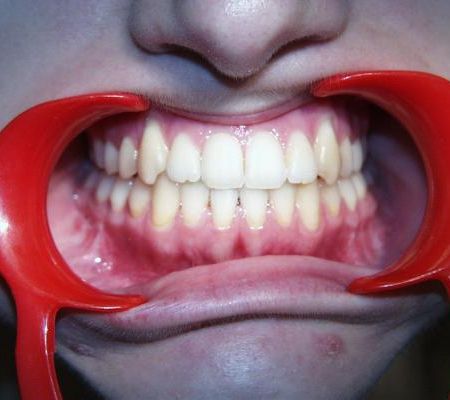

Während der Behandlung

Linkes Bild kurz vor, rechtes Bild kurz nach der Operation. Häufig ist noch eine weitere Anpassung der Zahnbögen und eine Feineinstellung der Verzahnung notwendig. In der Regel müssen die Patienten zwischen den Zahnreihen kleine Gummiringe einhängen, um die Kiefer in der gewünschten Position zu halten.